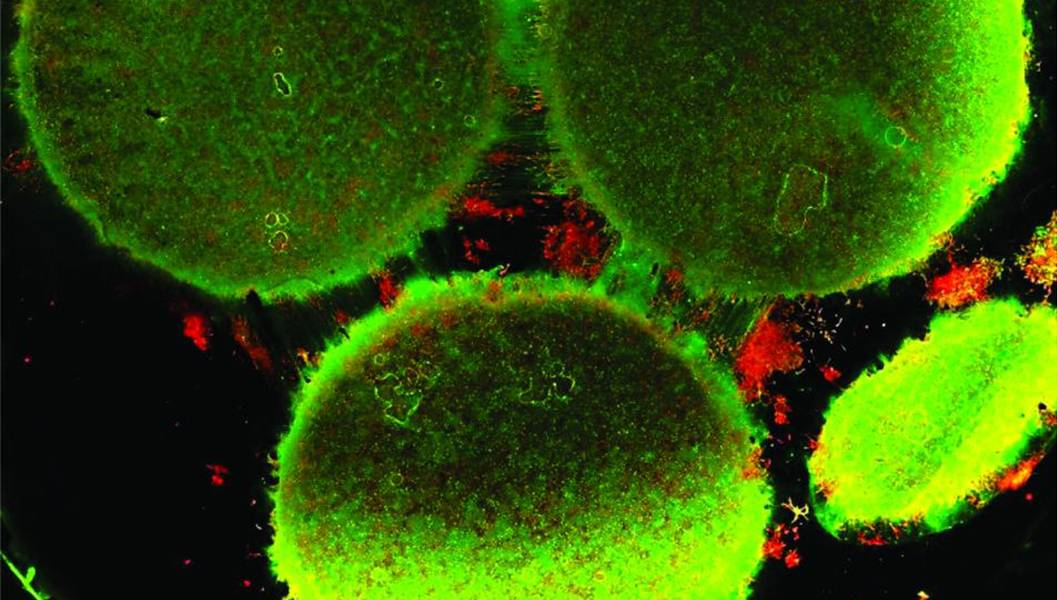

CREDIT: Disease Biophysics Group/Harvard University

The researchers modeled the three regions of the brain that are primarily affected by schizophrenia, namely the amygdala, hippocampus, and prefrontal cortex. The team characterized each region in vitro in terms of cell composition, protein expression, metabolism, and neural electrical activity. After that, they analyzed how neurons from each region of the brain changed when in communication with neurons from other regions.